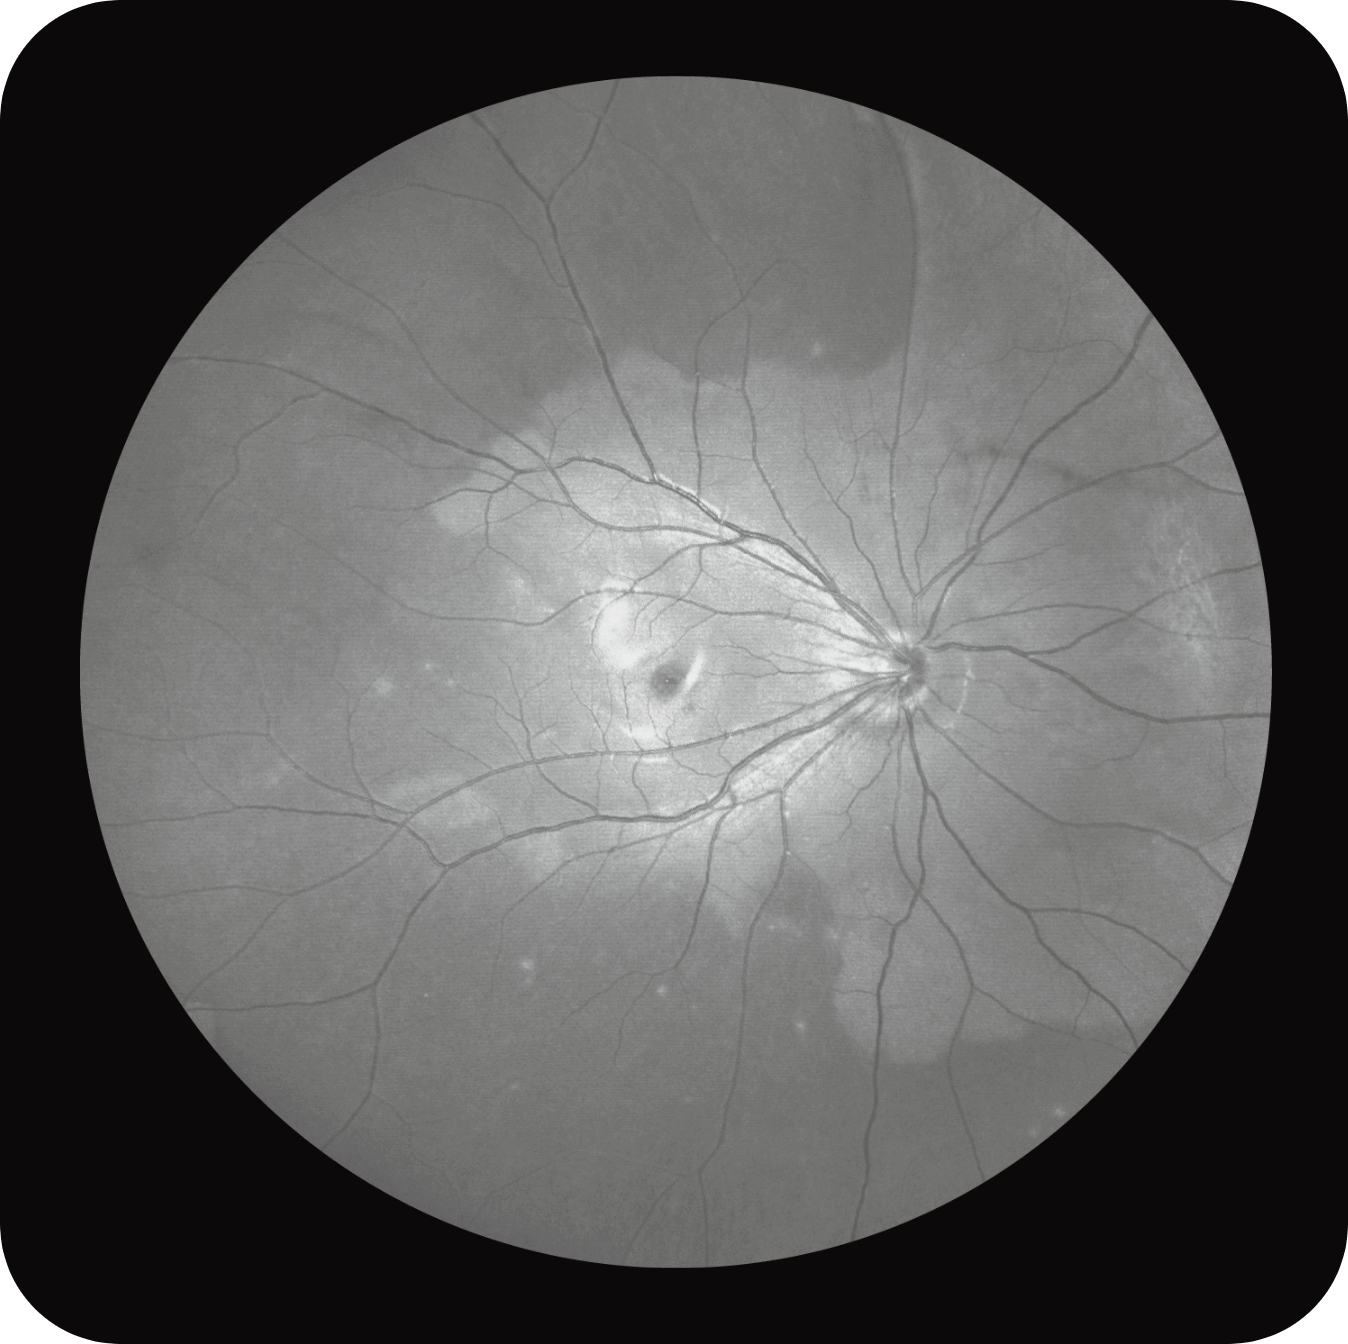

Olho Inteiro

Uma única varredura pode obter rapidamente imagens sincronizadas de imagens coloridas de campo ultralargo/FAF/FFA/ICGA e SS-OCT, alcançando sincronização em tempo real e alinhamento preciso de imagens planas e estruturais da retina, melhorando significativamente a eficiência da inspeção e otimizando o processo de diagnóstico e tratamento.” Uma única varredura pode obter rapidamente imagens sincronizadas de imagens coloridas de campo ultralargo/FAF/FFA/ICGA e SS-OCT, alcançando sincronização em tempo real e alinhamento preciso de imagens planas e estruturais da retina, melhorando significativamente a eficiência da inspeção e otimizando o processo de diagnóstico e tratamento.

Multi-Modalidade

Altamente integrado com tecnologias como SLO confocal e SS-OCT, ele combina imagens coloridas SLO de campo ultralargo, angiografia confocal a laser, autofluorescência e imagens tomográficas de segmento anterior e posterior ultraamplas e profundas em um único sistema.